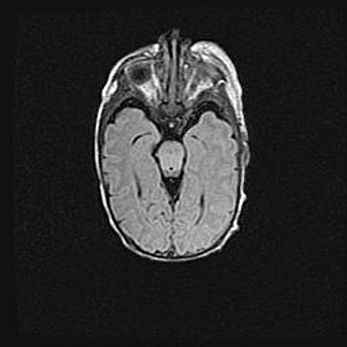

Наружная гидроцефалия с возможной атрофией височных областей.

Возраст: 28 дней

Вес: 3670 г

Пол: мужской

Окружность головы: 38 см

Срок гестации: 40 недель

Гидроцефалия головного мозга у новорожденных – это заболевание, которое характеризуется скоплением избыточного количества спинномозговой жидкости в желудочковой системе головного мозга в результате затруднения её перемещения от места выработки к месту поглощения в кровеносную систему или вследствие нарушения абсорбции. При открытой наружной форме гидроцефалии у новорожденных расширяются и переполняются субарахноидные пространства.

При нормотензивных  формах,  которые,  как  правило,  являются  следствием  перенесенных ишемических  повреждений  паренхимы  мозга,  возможно  сочетание микроцефалии  с нормотензивной гидроцефалией. В основе данных изменений лежит атрофия больших полушарий с преимущественной  локализацией  в  лобно-височных  областях.